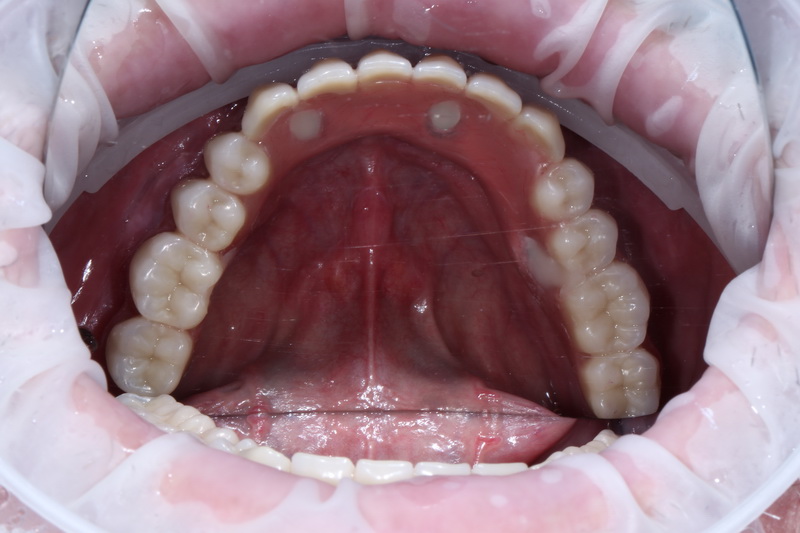

В день операції було проведено лікування, це – встановлення 4-х імплантів на нижній щелепі у попередньо сплановані позиції, з подальшим негайним навантаженням тимчасовим незнімним протезом.

Пацієнт чекає  2-го етапу, через 4—6 місяців, де плануємо замінити тимчасовий протез на постійний.  Таким чином, пацієнт жодного дня не залишиться без зубів.